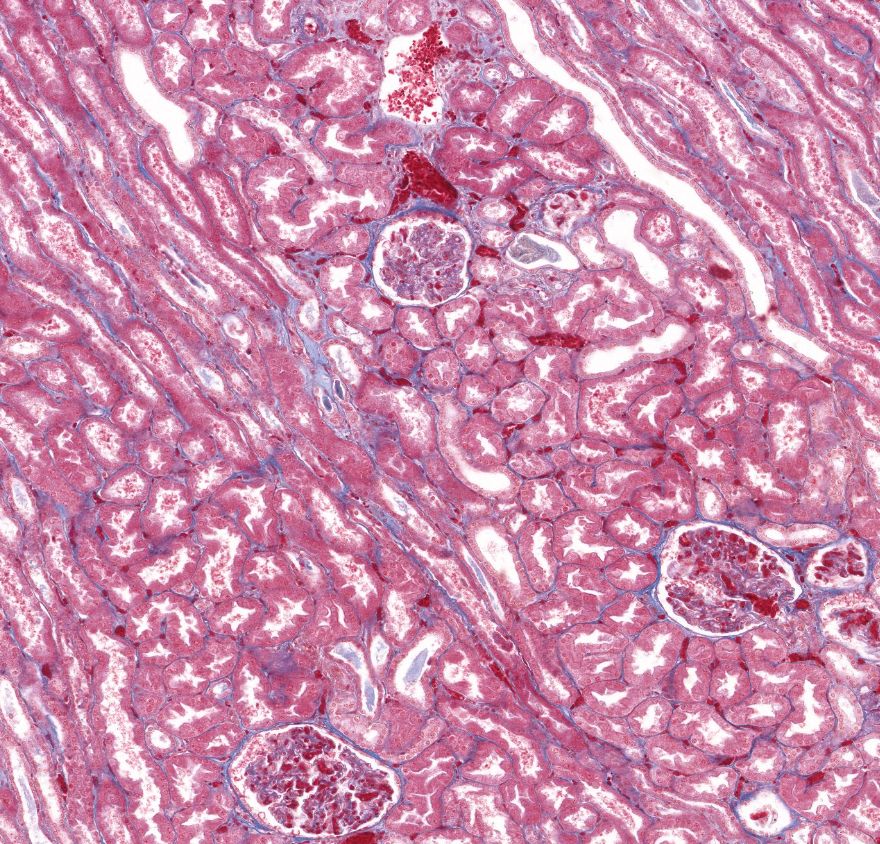

Córtex renal

Córtex renal

1: Corpúsculo renal

2: Cápsula

Córtex renal

Rim - corpúsculo renal